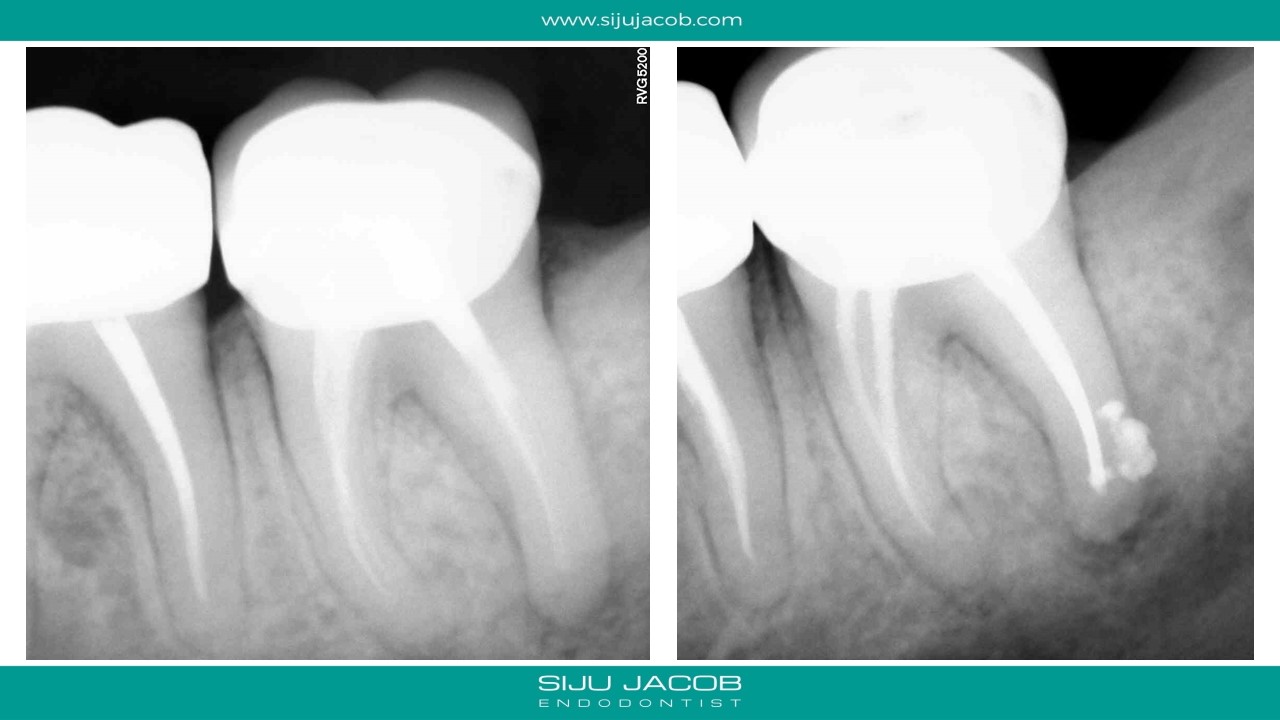

Selective Re-treatment of Distal Root

Patient came in with a sinus tract and lesion in the distal root. I Re-treated just the distal root alone. sinus tract disappeared after 2 weeks of Caoh.